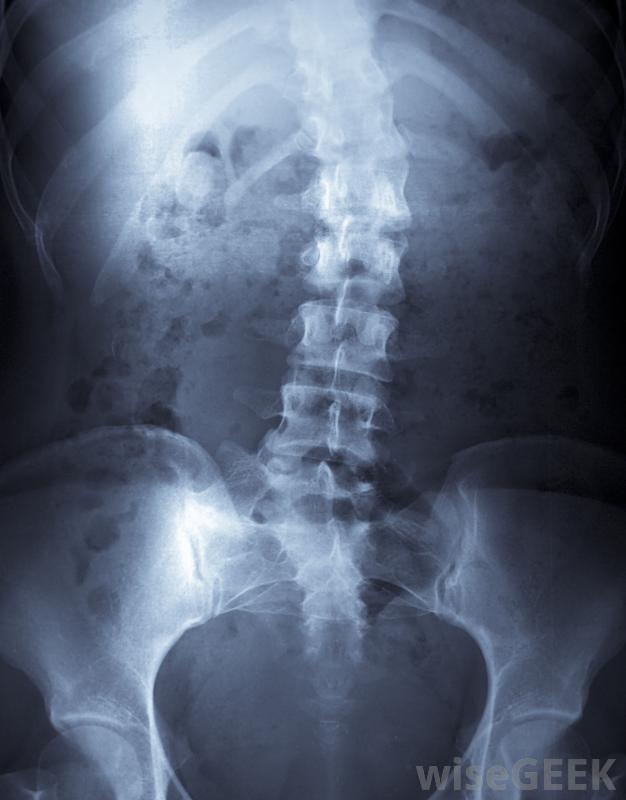

身体支撑架是背部严重受伤或脊柱侧凸等疾病患者佩戴的一种医疗器械,其作用是在脊柱愈合过程中,将脊柱的活动限制在一定范围内,根据患者的需要,可以用硬的和软的多种材料制成身体支架可用于治疗脊柱侧凸,这是脊椎的异常弯曲。要正确佩戴身体支撑,需要将几个部位固定在正确的位置。下部围绕着患者的骨盆区域,身体支撑的中间部分包裹着病人的腹部,身体支撑的上部固定在背部和肋骨上。可以佩戴身体支架来治疗严重的背部损伤。支架的每个部分都类似于一个外壳。包裹背部的部分的外壳包含左右两部分。支架的中心部分连接到支架通过两个旋转装置卡入到位。上部各部分的独立部分通过旋转装置固定在中间部分支架还有连接到上、下和中心部分的支架,以在佩戴过程中使设备保持在正确的位置。支架的设计和放置允许患者在使用支架时尽可能多地走动,而不会对脊柱造成损伤。虽然很少有人会说他们真正喜欢佩戴作为一个身体支撑物,替代品可能会对手术修复的脊柱造成足够的伤害,以至于需要进行另一次痛苦而昂贵的手术,或者无法治疗可能导致严重疼痛的医疗状况。考虑到这些可能性,在必要的治疗或恢复期间,几乎不间断地佩戴身体支撑架,这看起来并没有那么糟糕。在许多情况下,身体支撑物都能起到作用。脊柱手术后,如脊柱融合术,支架可防止患者脊柱侧凸,脊柱侧凸是指脊柱向左或向右弯曲超过10°的一种情况,一个支架可以帮助脊柱正确对齐,并使身体得到适当的发育。戴一个身体支架可能是一个长期的前景,但是是暂时的。大多数人在手术后痊愈或脊柱对支撑治疗有反应后,可以安全地取出支架。